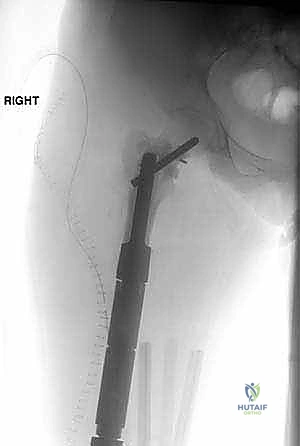

We have two main avenues for reconstruction: bulk allografts or modular intercalary endoprostheses. Most commonly, we lean towards bulk allografts, as they offer the potential for biological integration and long-term stability through osseous healing. However, allograft reconstruction isn't always feasible. In cases of poor host factors, such as compromised vascularity, small residual host segments, or in patients undergoing planned radiation or chemotherapy that could impede healing, an intercalary endoprosthetic reconstruction becomes our preferred option. This also holds true for patients who have experienced a prior failed allograft reconstruction. The beauty of modular intercalary prostheses is their inherent flexibility; they can be easily converted to a conventional endoprosthetic replacement, using joint-replacing modules at either end, either during the initial surgery or for future revisions.

Segmental prostheses offer immediate stable fixation, which allows for early rehabilitation and a rapid return of function. While aseptic loosening is a known complication with traditional endoprosthetic replacements, it is rarely, if ever, seen with intercalary implants. This is largely due to the absence of bearing surfaces that generate wear debris and the lack of exposure to joint fluid, both of which contribute to implant longevity. Newer implant designs have dramatically reduced the length of bone needed for stable fixation, thereby expanding the indications for these prostheses.

We also decide on the type and length of fixation. Plate fixation allows for standard osteosynthesis techniques and compression across the allograft-host junctions, which we believe improves healing. However, the screw holes created in the allograft are a recognized risk factor for late allograft fracture. Alternatively, intramedullary (IM) nail fixation, while potentially requiring additional incisions, generally provides stronger, more protective long-term fixation for the allograft without creating stress risers from screw holes. The challenge with IM fixation can be achieving compression at the host-graft junctions, which may impede healing. Sometimes, a combination of techniques is employed.